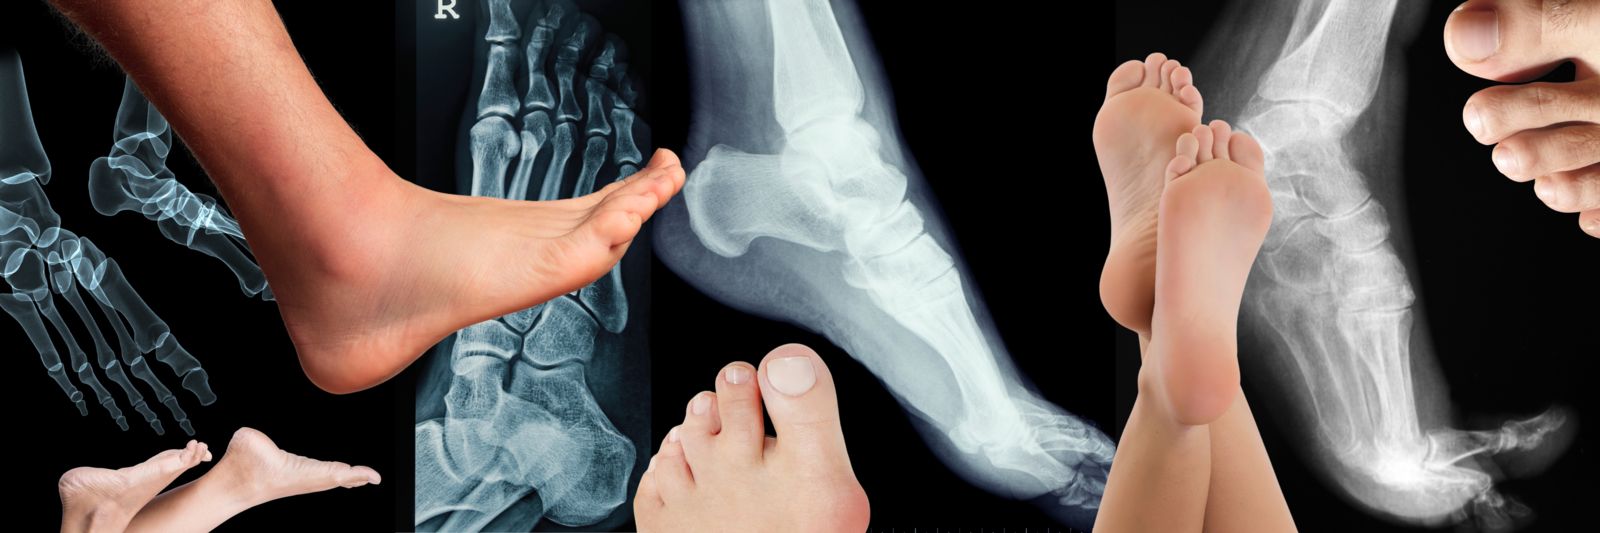

From stock.adobe.com

Film Xray foot radiograph show Flat foot deformity (pes planus or What Is Flat Foot Deformity Progressive collapsing foot deformity (pcfd), formerly known as adult acquired flatfoot (aaf), is a complex condition of the foot and ankle that results in flattening of the arch of the. It only affects 1 foot. All babies have flat feet. You often get feet or ankle injuries. Arches form during early childhood. You did not have flat feet before. A. What Is Flat Foot Deformity.